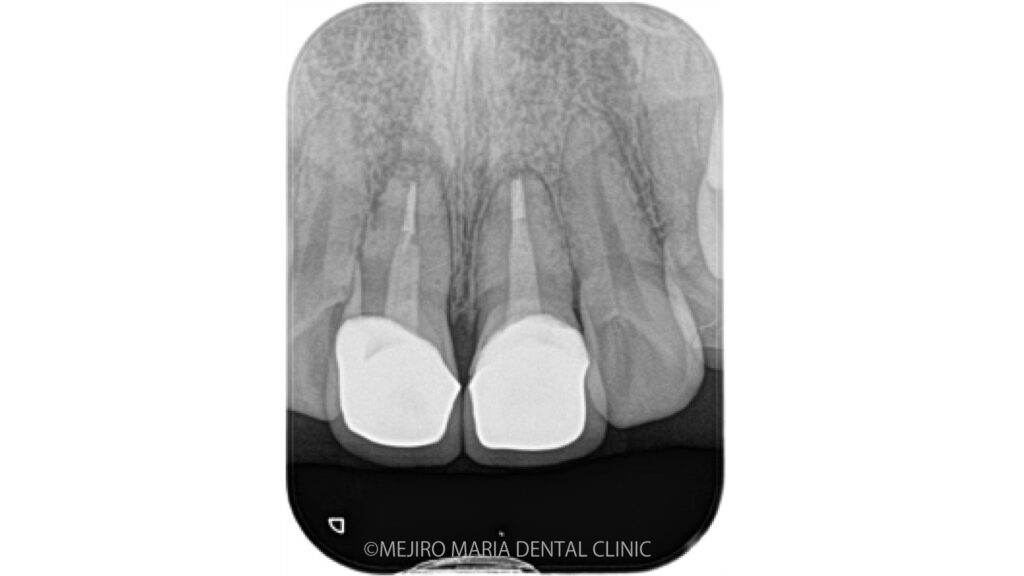

歯根端切除術の症例

【症例】セラミック治療後に発症した根尖性歯周炎に対する歯根端切除術

| 治療内容 | 歯根端切除術 |

|---|---|

| 治療期間 | 1ヶ月 (精密根管治療後2週間後に外科処置を行った) |

| 治療回数 | 1回(他、抜糸、術後3ヶ月後、1年後の経過観察等を除く) |

| 治療費用 | 220,000円(当院にて精密根管治療後2年内) |